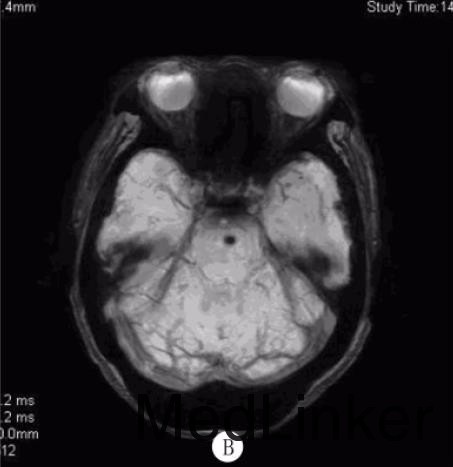

入院查体:BP158/98mmHg,神志清,构音障碍,双瞳孔等大等圆,对光反应灵敏,双眼各向活动充分,未见眼震,示齿口角不偏,伸舌居中,四肢肌张力正常,右下肢肌力4级,余肢体肌力正常,双侧病理征阴性,双侧感觉对称,颈软。急行颅脑CT 检查示:双侧侧脑室周围多发片状低密度影。颅脑MRI检查(距发病30余小时)示:双侧脑实质、脑干多发血管源性脱髓鞘,双侧基底核区多发脑软化灶,DWI序列可见脑桥偏左侧一圆形低密度灶,灶周稍高信号;SWI证实脑桥偏左侧及双侧基底核区多发顺磁性物质沉积。颅脑MRA检查示:颅内动脉粥样硬化改变。颈部血管超声检查示:双侧颈总动脉、左侧颈内动脉粥样硬化斑块(易损斑块)形成。

诊断:脑微出血?给予阿司匹林抗血小板聚集、阿托伐他汀稳定斑块、改善循环及对症支持治疗,病人右下肢无力稍缓解。5d后病人右下肢无力较前加重,查体示右侧肢体肌力3级,复查颅脑MRI示:脑桥偏左侧脑梗死。加用氯吡格雷抗血小板治疗,病人症状渐好转,病情平稳后给予降压治疗,出院时仍言语欠清,右侧肢体无力较前好转。

脑微出血(CMB)反映脑小血管疾病的出血倾向,是高血压性小血管病和脑淀粉样血管病的影像学标志,多被认为是无症状性的,缺乏急性临床表现。但WATANEBE等报道1例在中脑急性形成的CMB导致核上性眼肌麻痹,认为单个CMB在功能区急性形成也可能引发临床表现。此外,脑淀粉样血管病和高血压病人出现短暂性神经功能障碍也可能与CMB有关。该例病人首次出现右下肢无力时颅脑CT及MRI检查均未见明显责任病灶,但DWI序列可见脑桥偏左侧一圆形低密度灶,后经SWI检查证实为CMB。病人既往有高血压史,急性起病,脑内可见多发白质病变、腔隙性梗死等脑小血管病标志,但均非急性形成,在运动传导通路上可解释临床症状的仅有脑桥左侧CMB。由此推测其首次无力原因可能为脑桥单发CMB,此CMB与基底核区CMB影像学表现的不同可能反映了这两类CMB发生机制及病理学表现的差异,其病灶边缘呈环形DWI高信号也支持此CMB为急性形成。提示少数临床疑诊急性脑血管病的病人可能由急性CMB形成引起,对CMB的检测可能有助于诊断和鉴别诊断。但由于该病人发病前未行CMB检测,该单发CMB是否为急性形成尚不能肯定。DOI:10.13361/j.qdyxy.201502039